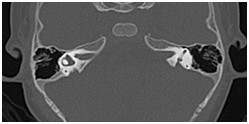

颞骨及耳(病例-前庭导水管扩大)